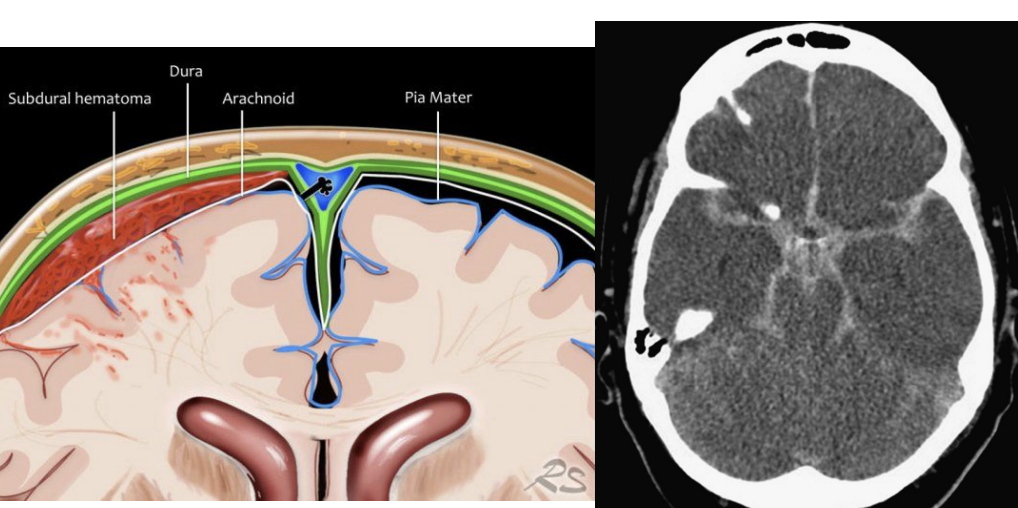

Brain Layers

dura —> thickest and most durable

arachnoid —> thinner than the dura

subdural —> below the dura

subarachnoid —> CSF

pia mater — >adheres to the surface of the brain (soft and fragile) blood supply to the brain

CLOSER TO BRAIN - WORSE DAMAGE

Types of brain hemorrhage

epidural hematoma

subdural hematoma

subarachnoid hemorrhage

intracebral hemorrhage

Extracerebral Hemorrhages

3 types depending on WHERE blood accumulates:

1. Subarachnoid hemorrhage-bleeding between arachnoid and pia. —> closest to the brain/blood supply

2. Subdural hemorrhage-bleeding beneath dura.

3. Epidural hemorrhage-bleeding between dura and skull.

● TBI usual cause of subdural and epidural hemorrhages

● After bleeding stops, left with a hematoma/bruise (subarachnoid, subdural, or epidural)--accumulation of clotted or partially clotted blood in the space created by the hemorrhage.